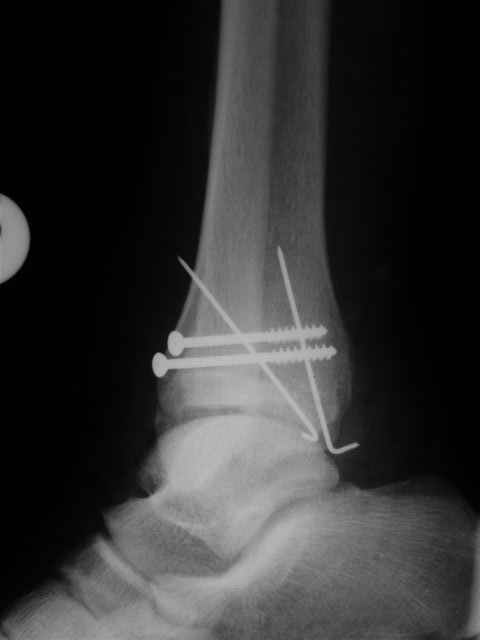

В первом письме я упомянул о закрытом повреждении правого голеностопного сустава, эверсионно-пронационный механизм травмы - перелом внутренней лодыжки( поперечный, на уровне суставной щели) и отрывной перелом бугорка Chaput. После обработки открытых переломов бедра и большеберцовой кости в эту же сессию перелом внутренней лодыжки фиксировал двумя расходящимися спицами, бугорок Chaput двумя тягловыми винтами 3,5 мм. Раны заживают благополучно. Учитывая повреждение наружной группы мышц, активное разгибание в голеностопном суставе ограничено. Пассивная + пассивно-активная мобилизация голеностопного сустава с физиотерапевтом.

Отправитель: Evgueny Tschekashkin 19 Декабрь 2004, 23:02

Уважаемый Иван,

Я предупреждал, что ничего сверхъестественного. Каюсь, что одна из спиц прошла несколько дальше, чем нужно было, но главное - перелом стабилизирован и больной работает суставом в полном объёме, несмотря на представленную раннее травму коленного сустава.